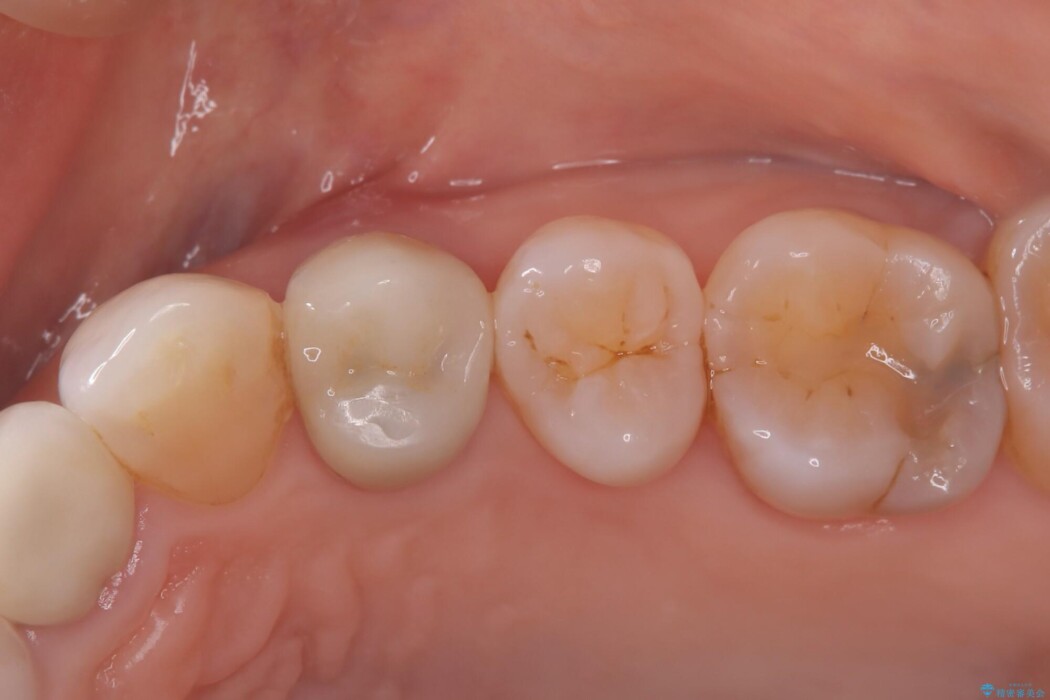

被せ物を除去し、マイクロスコープにて内部を強拡大で確認したところ、歯の根の深い位置まで真っ直ぐにひびが入っていることを確認し、保存が不可能な状態であったため抜歯をすることとなりました。

インプラント治療後は「長年悩まされた痛みから解放され、自分の歯と同じように食事ができるようになった」と喜んでいただけました。